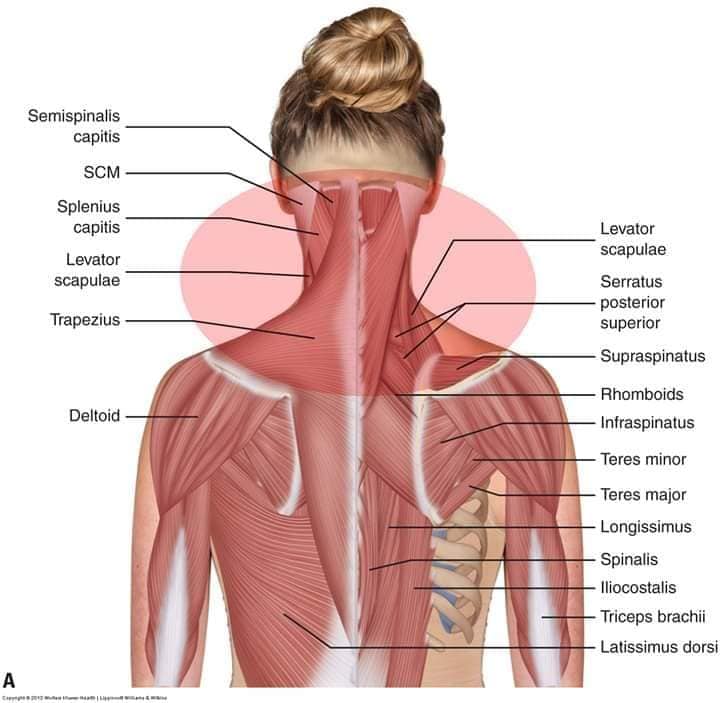

М'язи, що повертають голову: Стерноклейдомастоїдний м'яз: один з найважливіших м'язів, який дозволяє здійснювати повороти і нахили голови. Він походить від грудини та ключиці і прикріплюється до соскоподібного відростка скроневої кістки.

М'язи, що розширюють шию: М'язи, що розширюють шию: включають трапецієподібний м'яз, який бере участь у піднятті плечей і розширенні шиї.

М'язи, що піднімають лопатку: Трапецієподібний м'яз: великий м'яз, що покриває верхню частину спини. Його функція - підтримка і рух лопаток, а також забезпечення стабільності хребта.

М'язи, що ведуть лопатку до хребта: Широкий м'яз спини: великий м'яз, що розташований в нижній частині спини. Він відповідає за рухи плечей і лопаток, а також за розширення верхньої частини тулуба.